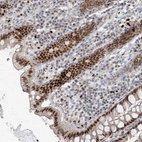

Immunohistochemical staining of human colon shows strong nuclear positivity in glandular cells.